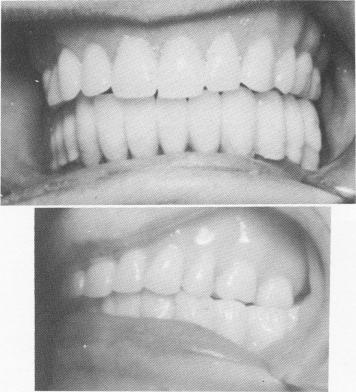

Fig. 13-48. The splint in position.

template (Fig. 13-43). These pins were extended deep into the bone, down to the cortical plate in the inferior portion of the mandible. The three pins were shortened to the height of the horizontal portion of the U-shaped bar (Fig. 13-44) and then bent anteriorly so that they fitted flush to, but underneath, the horizontal bar (Fig. 13-45). The three pins were fused together (using the brush-on technique) and to the entire inverted U-shaped bar with cold cure acrylic, thereby becoming an integral part of the template (Fig. 13-46). An all-acrylicover-gold full arch denture was then processed (Fig. 13-47). The bridge was used as a fixed removable denture and was set buccal to the mylohyoid ridge, instead of on it, to avoid further pain (Fig. 13-48). A Panorex shows the implants and prosthesis (Fig. 13-49) .